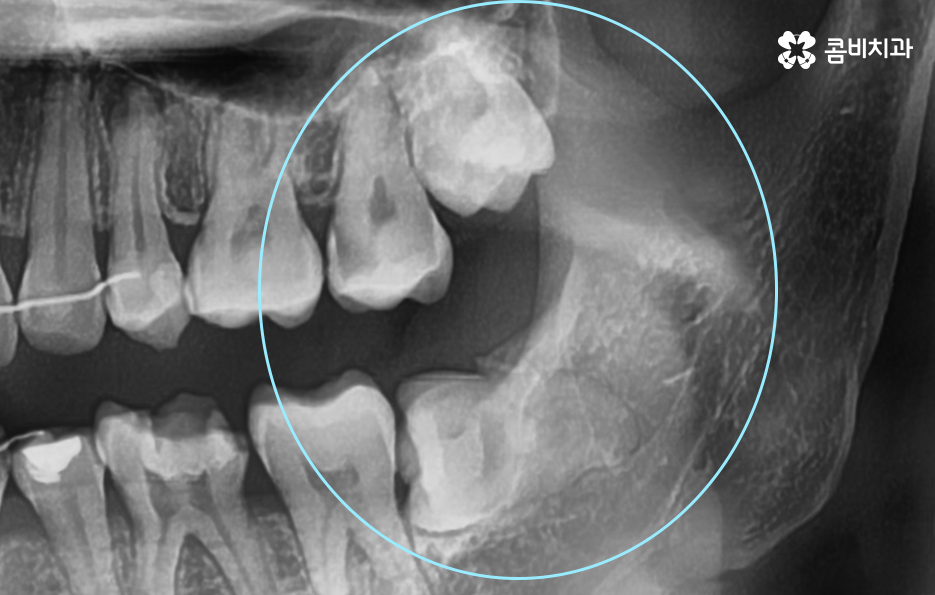

사랑니는 치아 중에서도 가장 마지막에 맹출이 되며 현대인들은 턱뼈가 좁아지는 추세이기 때문에 마지막에 자라는 사랑니는 위 케이스처럼 윗니의 경우 어금니의 높이 보다 다소 낮게 자라는 경우가 많고 아랫니의 경우 매복되어 있거나 누워서 자라는 사랑니의 형태로 자라는 경우가 많이 있는데요. 이러한 사랑니의 형태로 인해 어금니와 사랑니 사이에 이물질이 끼기 쉽고 칫솔질이 잘 닿지 않기 때문에 충치 뿐 아니라 잇몸 염증이 발생되는 경우가 많으며 사랑니 어금니 통증의 원인이 주변의 세균 증가로 인해 충치로 이가 썩은 경우부터 잇몸이 자주 붓고 염증이 심해지면서 통증을 느끼는 경우가 40,50대 이후에 흔하게 발생되는 사랑니와 인접한 어금니의 문제로 볼 수 있어요

일반적으로 30대 이후에는 치주질환이 급증하게 되는데 40,50대 이후에는 잇몸이 점점 내려 앉게 되고 부분적으로 맹출된 사랑니 주변 잇몸 역시도 조금씩 내려앉는 경우가 많이 있는데요. 사랑니 사진을 보시면 아시겠지만 일반적인 치아의 높낮이와는 달리 사랑니가 어금니의 뿌리 부분 정도 높이에 자리하고 있는 것을 볼 수 있어요.

일반적인 치아와 치아 사이는 이물질이 쉽게 침투하지 못하게 치아 사이의 공간이 많지 않고 치아 역시도 실링이 되어 있어서 미생물이 치아를 쉽게 뚫지 못하며 면역 물질로 인한 면역 작용도 있기 때문에 평소 칫솔질과 치실 사용, 주기적인 스케일링으로 어느정도 관리가 될 수 있는 것에 반하여 사랑니의 경우 어금니의 뿌리 부분에 가깝게 충치가 발생하기 쉽기 때문에 적절한 치료 시점을 놓치면 사랑니 어금니 통증이 두 치아 모두를 발치하게 되는 상황까지 발생될 수 있어요